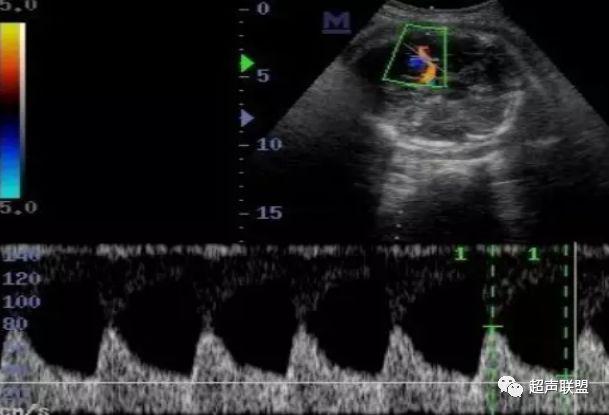

2 胎儿大脑中动脉测定

缺氧早期大脑血液供应增加,颅内血管扩张,阻力降低,舒张末期血流速度增加,PI、RI值下降,说明缺氧早期的血流再分配。当大脑中动脉RI、PI值明显下降,而脐动脉和腹主动脉的PI值升高,大脑中动脉PI值与脐动脉PI值的比值低于2个标准差时,提示严重缺氧的存在。

1、比值标准:大脑中动脉阻力降低,妊娠期,大脑中动脉RI <脐动脉RI;

4、当大脑中动脉RI及PI值明显下降,而脐动脉及腹主动脉的PI值之间升高,大脑中动脉PI值与脐动脉PI值低于两个标准差时,提示为胎儿严重缺氧;

2、大脑中动脉血流阻力降低;

图3 正常大脑中动脉血流频谱

图4 大脑中动脉血流阻力减低